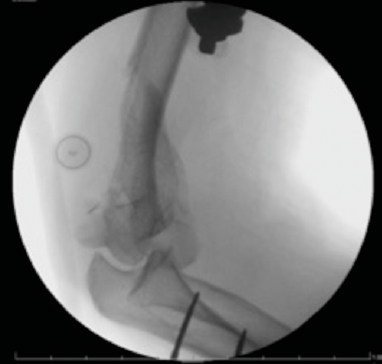

Figure 5.X-ray after fracture reduction and stabilization with an external fixator.

The patient was urgently taken to the operating room for reduction and stabilization of the fracture with external fixation (Fig. 5). At the end of surgery, there were no clinical signs of ischemia and a check of the radial artery with Doppler ultrasound showed recovery of blood flow. Given this condition, the vascular surgeon did not make surgical a indication. Sodium heparin infusion was started with aPTT target between 50 and 60 sec.